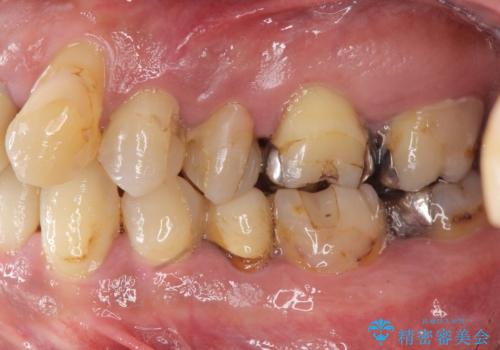

- 歯が全体的に揺れ始め、恐怖を感じ他院に相談に行ったところ、全体的な歯周病の問題・抜歯の必要性・入れ歯の提案を受け、入れ歯以外の選択肢を希望され来院されました。

全体的な歯周病検査を行い、多数の残すことのできない抜歯の必要な歯を認めたため、残せる歯に対しての徹底的な歯周病治療、失った歯に対しブリッジ・インプラント治療を全顎的に行っていくこととしました。